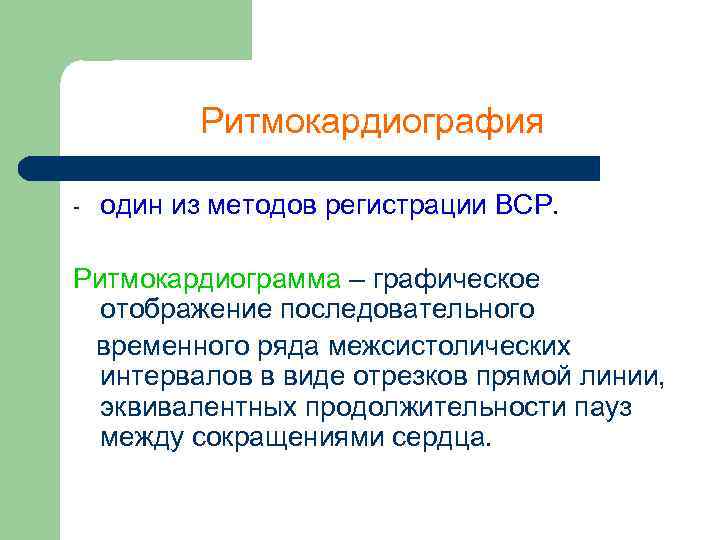

Ритмокардиография - один из методов регистрации ВСР. Ритмокардиограмма – графическое отображение последовательного временного ряда межсистолических интервалов в виде отрезков прямой линии, эквивалентных продолжительности пауз между сокращениями сердца.